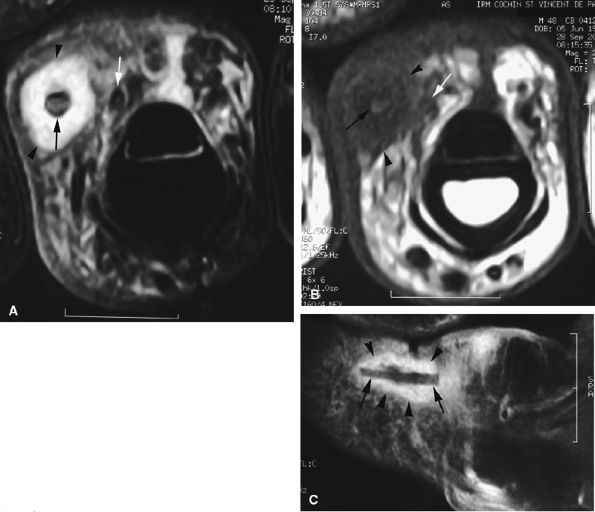

FIGURE 11.20 ● Acute injury of the radial collateral ligament (RCL) of the PIP joint of the fourth finger. Coronal (A) and axial (B) post-contrast fat-suppressed T1-weighted images displaying distal avulsion of the RCL with a proximal retraction (black arrows). The retinacular apparatus is displaced (arrowheads) with periligamentous edema. The ulnar collateral ligament is also identified (white arrows).

|